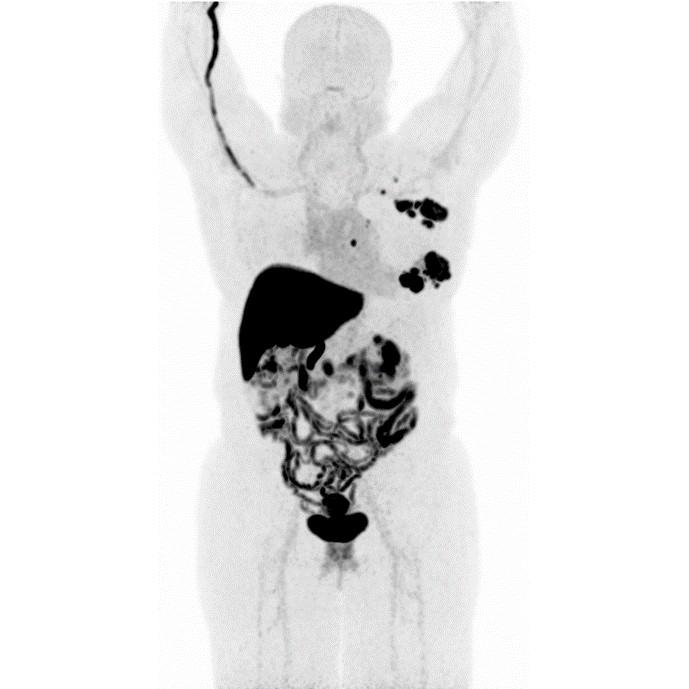

Partial nml and melanoma PET scan

The goal of PET/CT imaging in oncology is to enable the physician to distinguish between benign and malignant pathologies, to determine the extent of disease, to detect residual and recurrent tumors, to monitor the effectiveness of treatments, and to guide therapies.